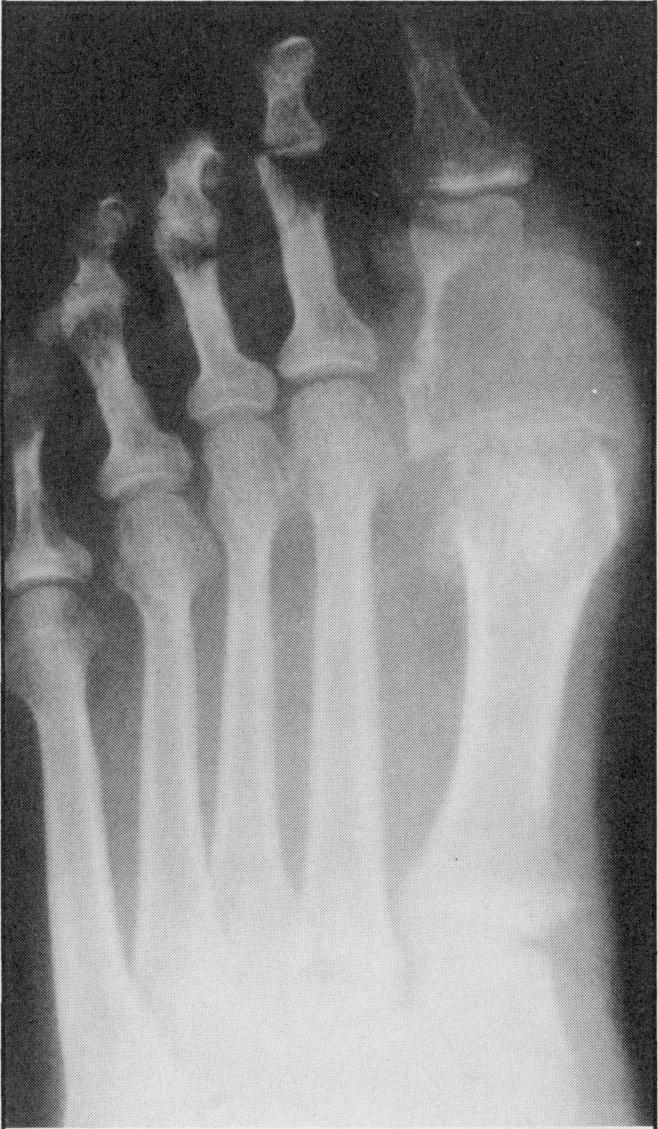

Although metastases to bones from solid tumors are very common, involvement of small bones of the hands and feet is extremely rare. One half of the cases reported in literature resulted from a primary tumor in the lung. Four cases seen over the last four years with metastases to bones of the hand and one case with metastases to foot bones are discussed. None of these patients had a lung primary tumor. Three of the four patients who had metastases to hand bones had the disease on the right side.

尽管实体瘤骨转移很常见,但手足小骨受累极为罕见。文献报道的病例中有一半源于原发性肺癌。本文讨论了过去四年中见到的4例手部骨转移病例和1例足部骨转移病例。这些患者均无原发性肺癌。4例手部骨转移患者中有3例病变位于右侧。